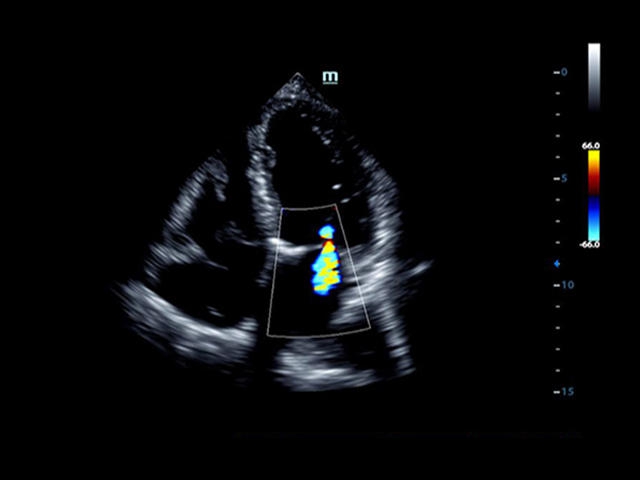

Mindray DC-8 Exp оснащен новым поколением датчиков с увеличенным количеством элементов и инновационной технологией "3T". Это позволяет достичь высокой детализации и качества изображения. Благодаря новейшей технологии iFlow, можно визуализировать даже самые мелкие сосуды и кровеносные пути.

Сверхширокополосная нелинейная обработка изображений снижает визуальные шумы на 30% по сравнению с другими системами. Технология iClear позволяет устранить зернистость изображения, а iBeam (технология пространственного компаундинга) обеспечивает высокое качество сканирования органов и тканей под различными углами.